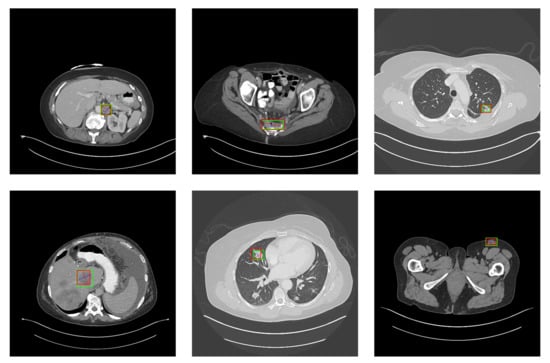

5.2. Detection Results

For further comparison, we extracted six images from the CT image series of DeepLesion. These images were taken from different sites of lesions and different areas of lesions, showing the detection results of the comparison model as comprehensively as possible. Figure 10, Figure 11, Figure 12, Figure 13, Figure 14, Figure 15, Figure 16, Figure 17, Figure 18 and Figure 19 show the detection results. All green boxes represent ground truth; red boxes denote predicted bounding boxes. It can be seen that Faster-RCNN performs very poorly on small lesions and lesions that are not easy to identify, while YOLO v3, YOLO v4, and SSD series perform relatively well. However, the aspect regression of the bounding box at small lesion locations is still not accurate. On the other hand, EfficientDet, Mask-RCNN, and YOLO v5 perform relatively well and detect lesions accurately. This may be related to the attention extraction module in these networks.

Figure 13.

The detection results of Faster-RCNN in the DeepLesion dataset. The green box marks the location of the lesion.